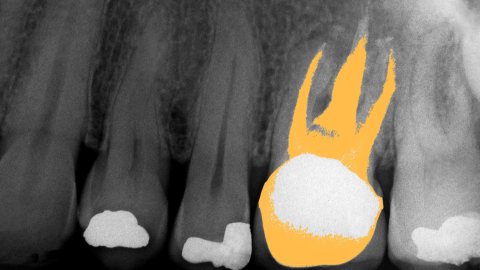

Dental X-Ray showing the upper jaw of a 55-year-old male. One tooth has had a root canal operation performed, and the adjacent teeth show a total of three filled cavities. (Getty)

1. When cavities are drilled out, sometimes the fillings don’t stop the decay process. If that goes on long enough, then eventually, the tooth will need to be drilled out/excavated all the way through the root. This removes blood vessels, nerves, and connecting tissue (all of this is known as the pulp). A tooth that has this procedure done to it is effectively dead because the material used in fillings will kill organic cells.